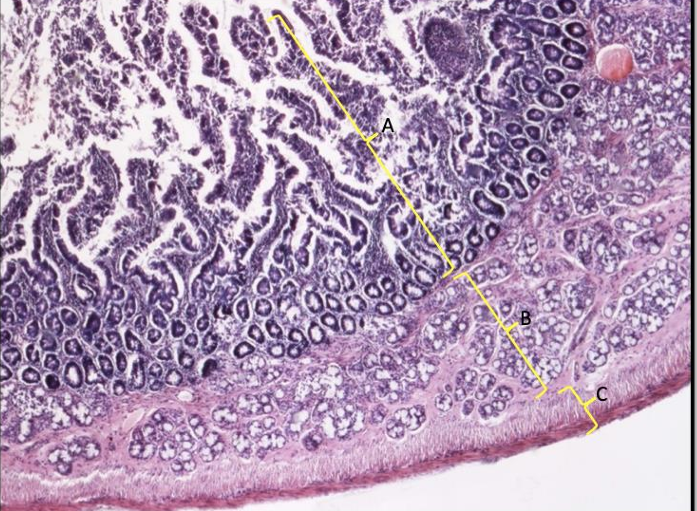

jelito nr 303

jelito cienki 405

kosmki jelitowe

tkanka łączna = błona śluzowa z komórkami kubkowymi i kryptami Lieberkuhna

tkanka łączna błony śluzowej

błona podśluzowa

mięśniówka okrężna i podłużna

błona surowicza

dwunastnica nr 321

błona śluzowa z kosmkami

błona podśluzowa z gruczołami brunnera

mięśniówka